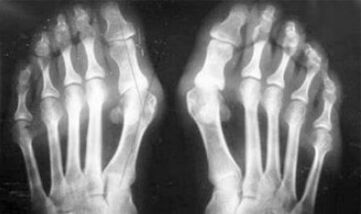

- Breach of metabolism (gout).

The difference between arthritis and the arthrosis of the fingers and hands of the hand is that the first disease is cured and other is not.They touch with arthritis, sinovial shell and the capsule of the wrist.

The defeat of cartilage and bone tissue occurs only in the late phases in the neglected state.With arthrosis, the cartilage tissue is first affected, and then the bone, the inflammation of the sinum membrane is secondary origin, ie it develops against their background.